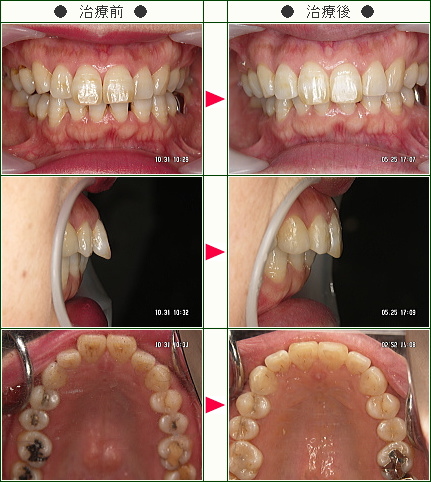

「自然に歯の手入れにも熱心になったことも収穫の1つです」M.W様 58歳 女性

この年齢で矯正治療にトライしようとは自分でも驚きでした。

歯周病、虫歯などもあり、先生泣かせの患者だったと思いますが、いつも誠意を持って接して下さった皆様に感謝の気持ちでいっぱいです。

部分矯正ですので完璧とは言えませんが、笑顔もきれいになり自分自身では満足しています。

拡大床の時期は話しづらく、辛いこともありましたが、マウスピースになってからは外からは殆どわかりませんし、滑舌にも問題がなく、歌うことにも(時々オペラの舞台があるのですが)全く影響ありませんでした。

そして自然に歯の手入れにも熱心になったことも、収穫の1つです。

本当にありがとうございました。